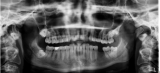

X-RAY能拍出骨骼和牙齿的照片,这是为什么呢?

X-RAY也就是X射线,X射线是一种波长很短的电磁波,其波长比可见光短得多。同其他电磁波一样,X射线也具有波粒二象性,即同时具备波和粒子的特性。人体软组织和骨骼吸收X射线的能力不同,因此X射线可用来检查人体结构。 2022-06-02 X射线